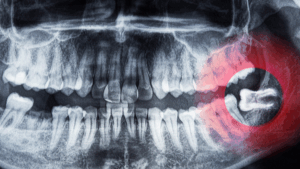

The presence of wisdom teeth can be confirmed through dental X-rays. These images allow our experienced dentists at WeSmile Dental Care to see if wisdom teeth are developing and determine their position in your mouth.

- Full-Mouth X-Rays: We utilise advanced imaging technology to get a complete view of your dental structure, allowing us to assess the position and development of your wisdom teeth accurately.

Wisdom Teeth Causes Impaction:

Wisdom teeth often don’t have enough space to emerge properly, leading to impaction. This means the teeth can become trapped beneath the gum line or grow at an angle, causing pain and potentially damaging adjacent teeth.